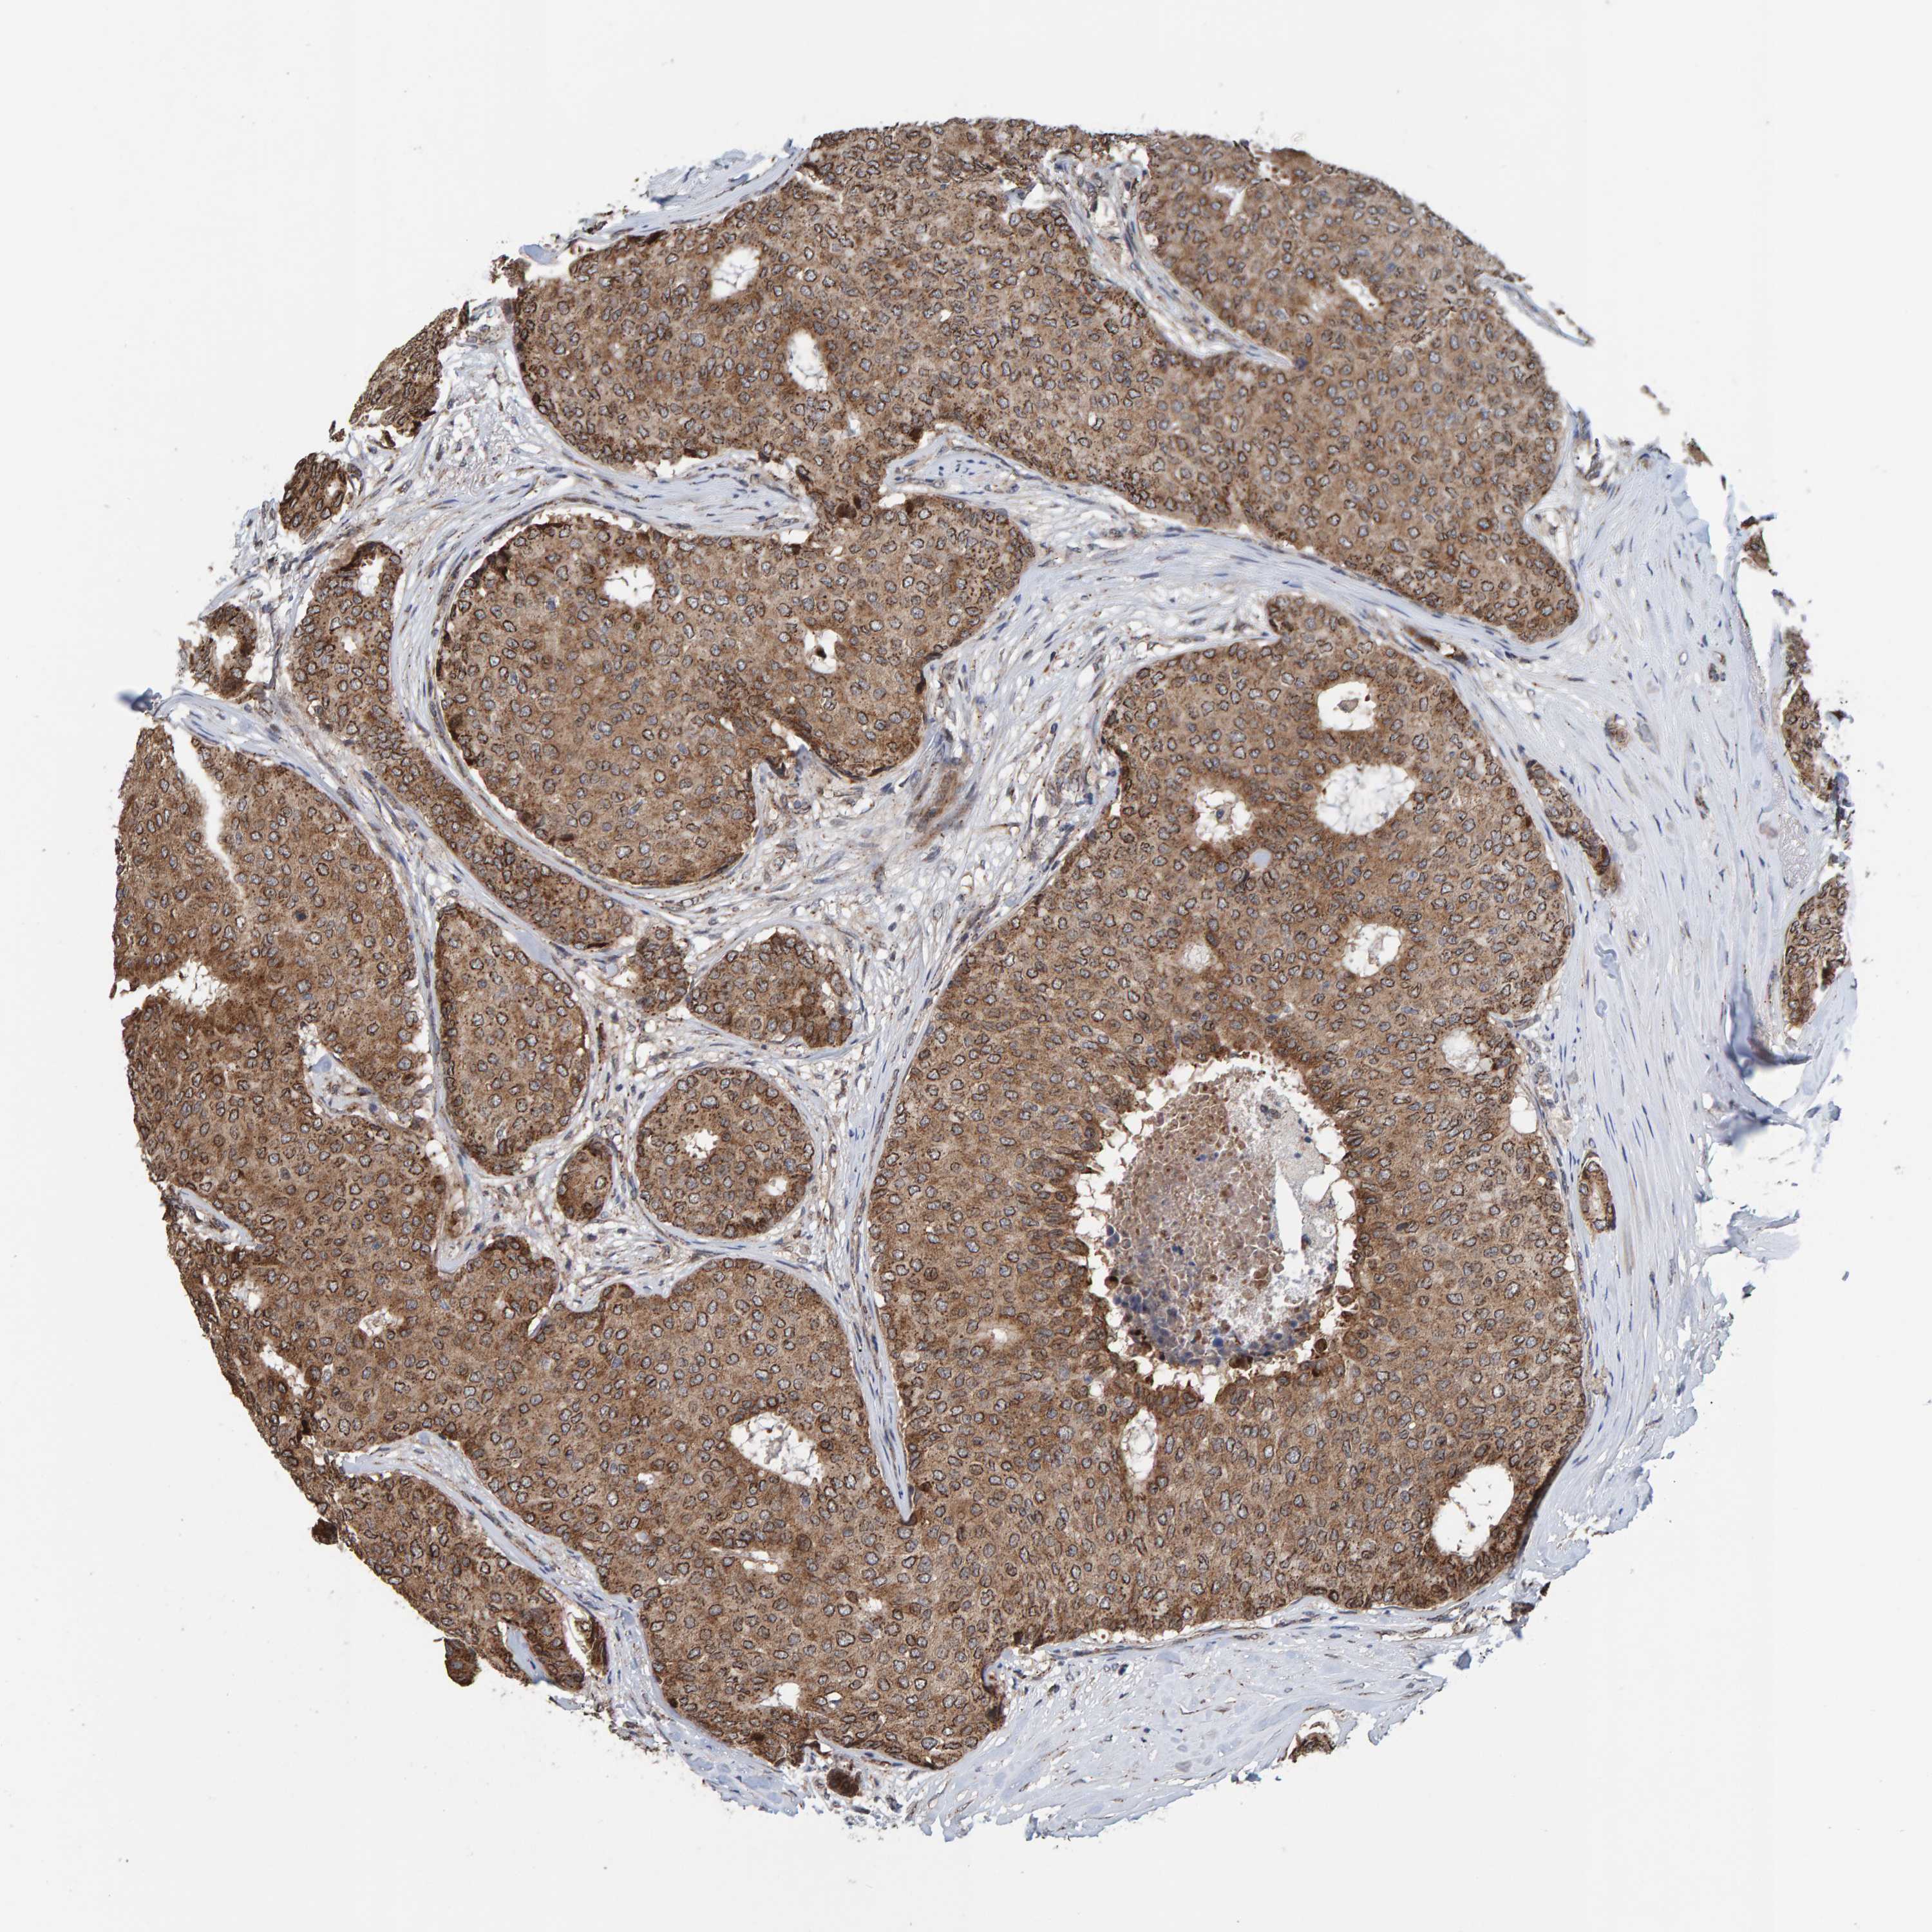

CANCER BREAST CANCER Show tissue menu

Breast cancer

Human cancer